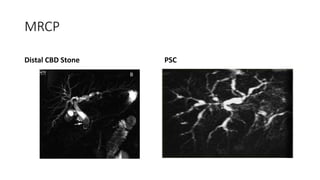

MRCP(Magnetic Resonance

CholangioPancreatography)

• MRCP is based on principle of

visualization of ducts containing

bile on T2 Weighted Images.

• Advnatages:

1. Non Invasive

2. No Contrast media is required.

3. Will show both upper & Lower

level of obstruction .

4. Excellent ductal anatomy is

visualized .

MRCP

Distal CBD Stone PSC